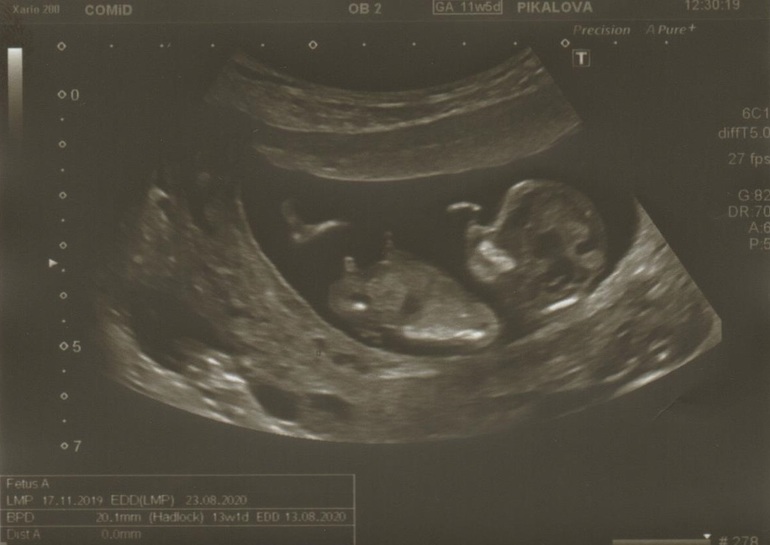

Первый скрининг пройден. Пол

УЗИ, КТГ, доплерФуф,я спокойна) Сердечко бьётся, все хорошо,чсс 161) Но,я ходила по ОМС, и меня это не устроило. Буду ждать 16 недель и пойду в другое место) Мне тут даже не показали😥Посмотрели все очень быстро,минут 5 наверное не прошло. А теперь,самое интересное) Предподожили мальчика,как я и думала) Буду ждать следующего скрининга,чтоб наверняка знать и приступать к покупкам 🤗 Девочки, а кто понимает? Я что то тоже мальчика вижу 😍

Почему все видят парня? Вот же половой бугорок,он параллелен позвоночнику ,у девочек же так?

В 12 недель же нет пипирки ,а половой бугорок не таких размеров

Если б больше срок был ,то ещё можно подумать,но тут мне кажется это не оно

Не, торчит). Знаете, сколько я узи пересмотрела за все свои беременности, не счесть 😁. Если девчонка все таки , то прям боевая будет)